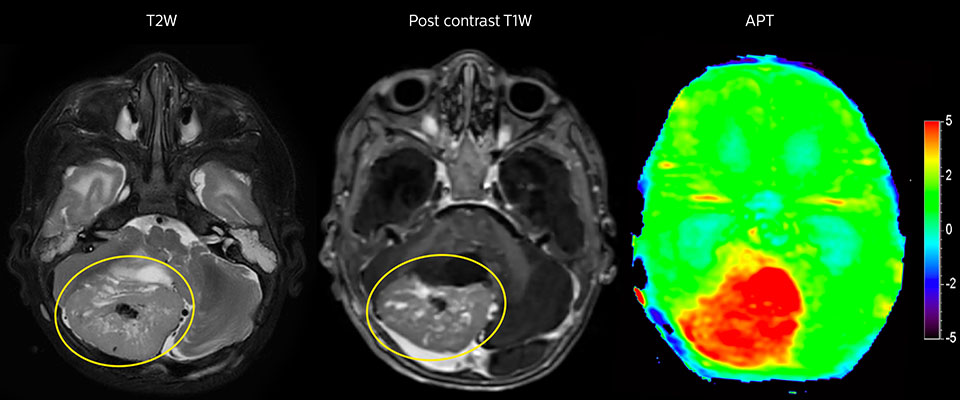

Tumor evaluation in a 1-year-old child with medulloblastoma. This aggressive tumor type is very solid and homogeneous. The high APT signal corresponds with the post-contrast image of this high-grade tumor.

Tumor grading can affect critical decision making The choice of treatment paths often strongly depends on the tumor grade. Common treatment options for high-grade tumors include surgical tumor resection followed by additional therapy such as radiation and or chemotherapy. Quick and decisive action is desirable in these cases as median survival for glioblastoma, for instance, is between 12.6 and 14.6 months, although longer rates have been reported.[8,9] Given the lower tumor growth rate of low-grade tumors, a range of potential treatment options exist for these cases. The selection of the most appropriate treatment is based on the balance of therapeutic benefits and side effects. At times, surveillance imaging may play a role while the choices of definitive therapy are being considered.[10] MR imaging is often used by radiologists and physicians in estimating the grade of brain tumors, but there is sometimes still uncertainty.[9,11] Differentiating between low-grade and high-grade tumors is not straightforward, even for the highly experienced radiologist. Gadolinium enhancement is not always specific for tumor grade, as some high-grade tumors demonstrate no gadolinium enhancement and certain low-grade tumors occasionally enhance (e.g. DNET). Gadolinium enhancement also occurs in any area of a blood-brain barrier disruption, such as treatment-related injury.[12] The power of APT for grading brain tumors with MRI While the gold standard for grading of gliomas is histopathology after biopsy, MRI is often used in monitoring glioma patients, and APT can be a valuable addition to the MRI exam in these patients. Tumor grade and APT signal have been observed to be commonly positively correlated: high-grade tumors tend to exhibit a high APT contrast.[12-15] APT images can be seen to visualize tumor with more emphasis than post-contrast images, resulting in a scan that may be easier to interpret. Scientific studies comparing tumor grades with APT signal in adult glioma suggest that APT can support tumor grading, separating high-grade from low-grade, even when traditional MRI is inconclusive.[5,13,14]